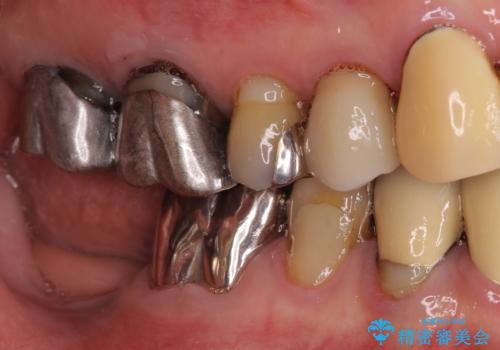

- 他院で抜歯が必要と診断され、インプラント治療を希望して来院された患者様です。

より審美的で、より機能的に優れた治療をご希望とのことであったので、ジルコニアカスタムアバットメントを用いたインプラント治療を行うこととしました。

ジルコニアカスタムアバットメントは、歯肉ラインに金属が見えにくいというだけでなく、クラウンを装着する土台の形が天然歯と近い形態となるため、清掃性が高く歯肉が腫れにくいというメリットがあります。

インプラントは、人工骨を用いた際の骨誘導能が比較的高いとさせるストローマン社のSLActiveを使用しました。